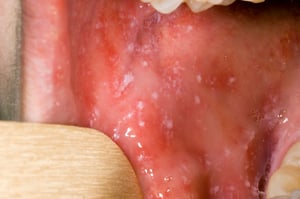

قبل بدء الطَّفح الجِّلدي، قد تظهر بقع كوبليك (Koplik spots) داخل الفم.بقع كوبليك هي بقع صغيرة، حمراء فاتحة ذات مراكز بيضاء أو بيضاء مزرقة.يمكن لهذه المراكز أن تشبه حبَّات الرمال.

بقع كوبليك هي بقع حمراء فاتحة ذات مراكز بيضاء أو بيضاء مزرقة قد تشبه حبات الرمل.قد تظهر هذه البقع في أي مكان من أفواه الأشخاص المصابين بالحصبة.

Koplik spots are bright red spots with white or bluish white centers that may resemble grains of sand. They may occur anywhere in the mouth in people who have measles.